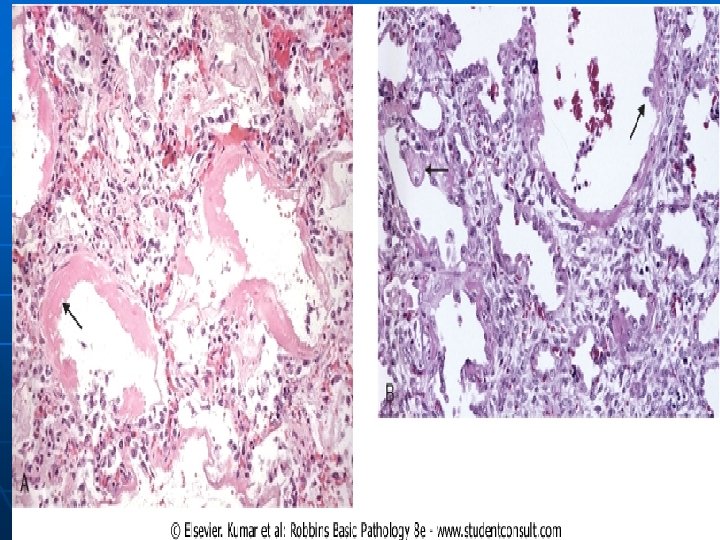

Morphology In the acute phase of ARDS - Microscopically, there is: a. necrosis of alveolar epithelial cells, b. interstitial and intra-alveolar edema and hemorrhage, and (particularly with sepsis) collections of neutrophils in capillaries. n

The most characteristic finding is the presence of hyaline membranes, particularly lining the distended alveolar ducts. - Such membranes consist of fibrinrich edema fluid admixed with remnants of necrotic epithelial cells. a.

In the organizing stage there is a. marked proliferation of type II pneumocytes in an attempt to regenerate the alveolar lining. b. Resolution is unusual; more commonly there is organization of the fibrin exudates, with resultant intra-alveolar fibrosis. n